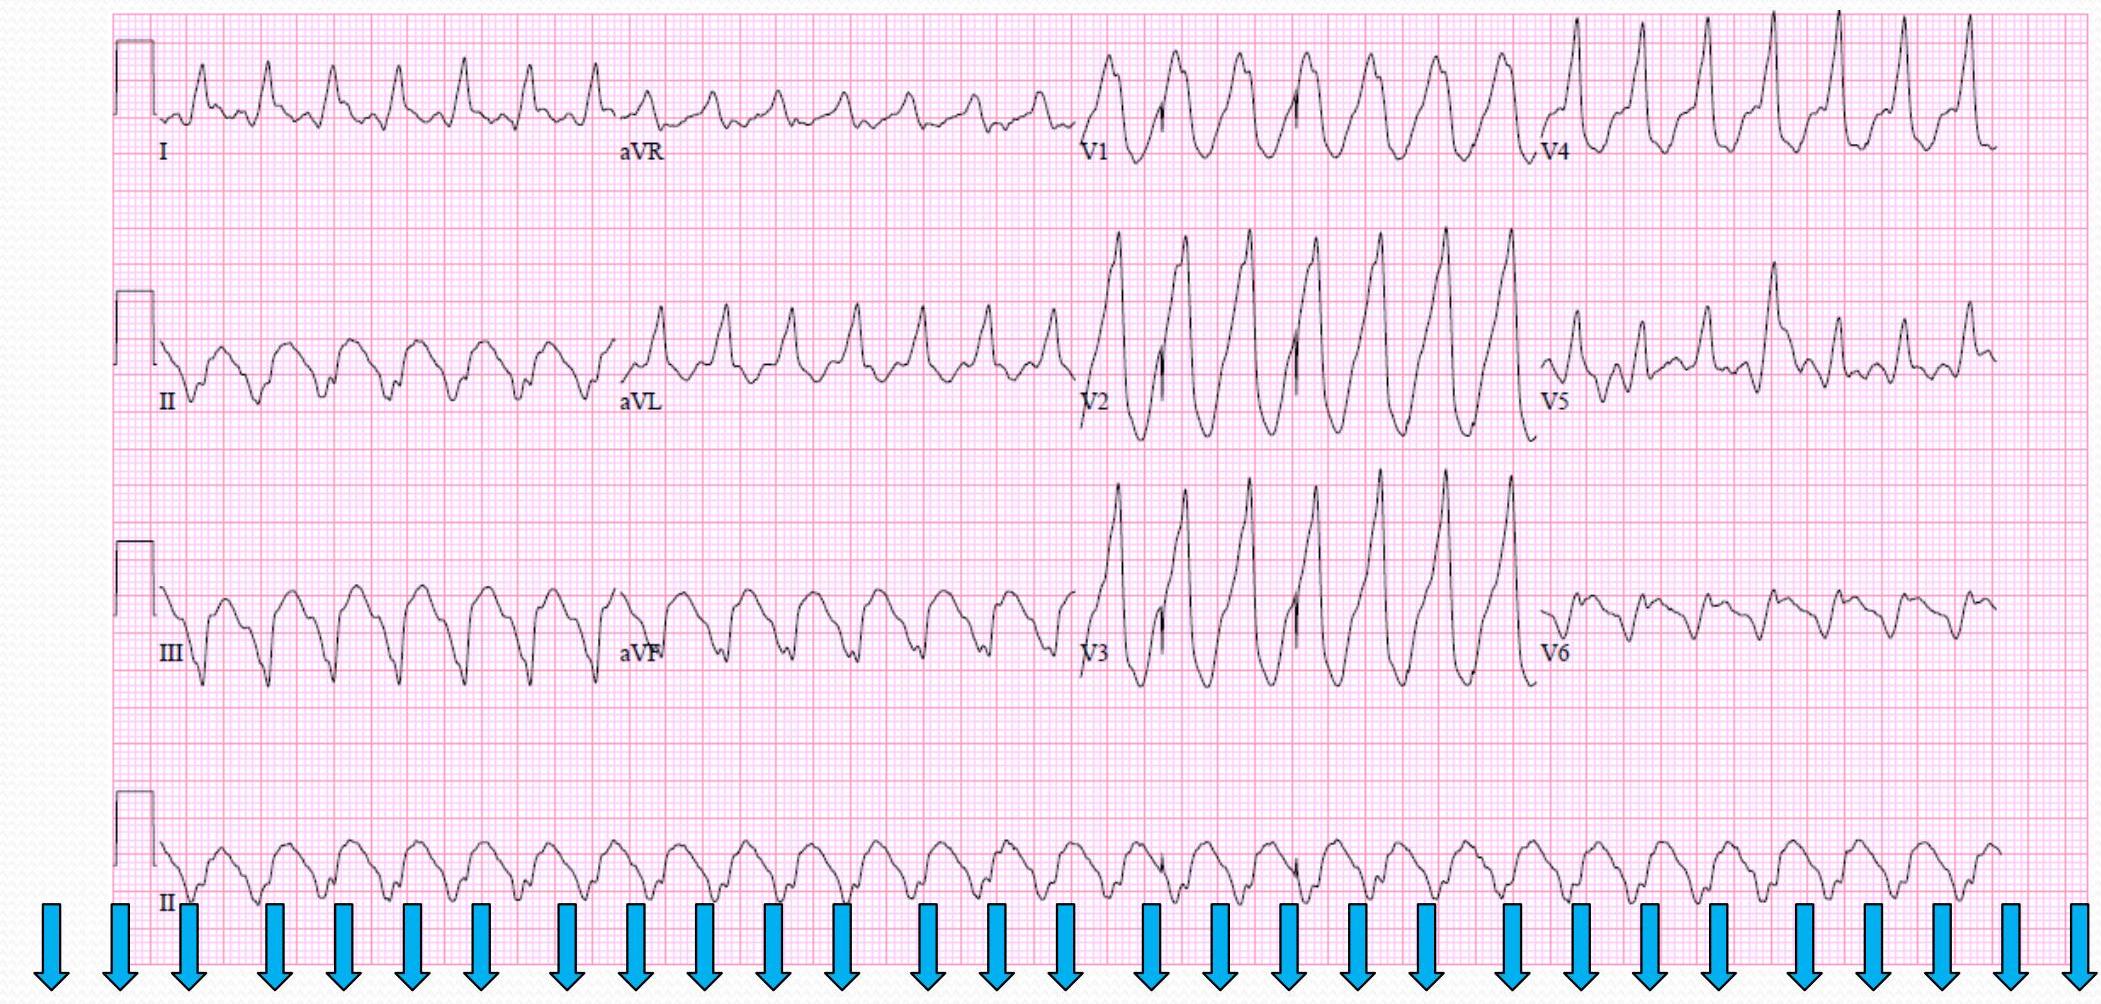

Ventricular Tachycardia (VT)

What do you notice?

- no Pwowe

- wide QRS → v Tach

- monomorphic

- Rates range from 100-250 beats/min

- Non-sustained or sustained

- P waves often dissociated (as seen here)

Monomorphic VT

What is the mechanism?

Treatment:

- ekt: Amidoron → IV line in lcu pn

- still more: Puls → cardioversion

- no Puls → defib

Polymorphic VT

- no P wave

- wide QRS